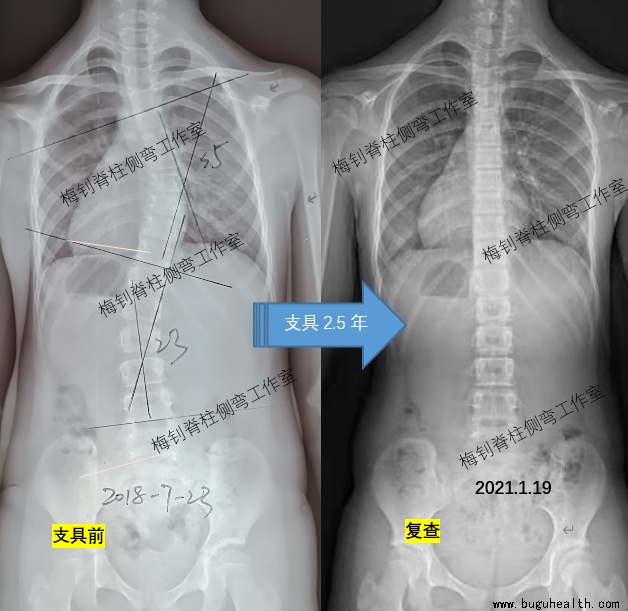

以下患儿,10岁发现侧弯,穿戴支具2.5年,脱支具48小时后拍片,脊柱保持竖直。开始减少穿戴时间,为脱支具做准备。